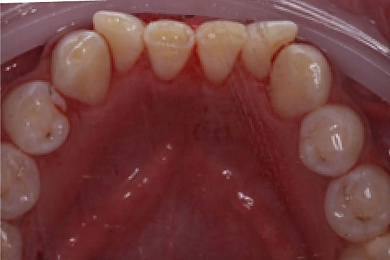

Нередко даже при хорошей гигиене полости рта на зубах образуется мягкий налёт, который в дальнейшем покрывает весь зуб и начинает отвердевать, постепенно превращаясь в зубной камень, который может провоцировать многие заболевания зубного ряда некариозного характера.

- При помощи специального ультразвукового скайлера бережно удаляются крупные зубные камни: это происходит при помощи создаваемых скайлером колебаний, который буквально «сбивает» каждый камень.

Результат лечения